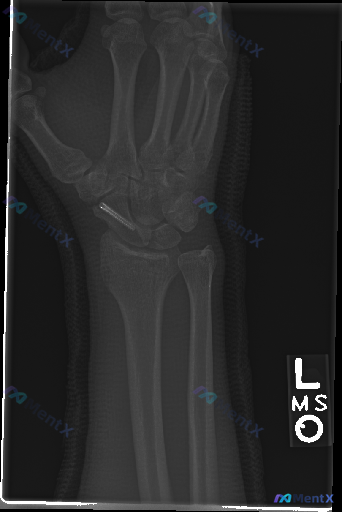

这张左手腕X光片的术后改变,你认为第一优先级需要警惕的是什么?

整理到一份左手腕正位X光片的术后复查影像资料,先把看到的客观表现梳理一下:

- 舟骨部位可见一枚金属内固定螺钉,位置大致沿舟骨长轴,螺钉本身未见明显断裂或移位;

- 舟骨处骨折线模糊,其余腕骨未见明确新鲜骨折线;

- 桡骨远端关节面有轻微形态改变,尺骨茎突可见边缘平滑的陈旧性断裂迹象;

- 腕骨间关节、桡腕关节、下尺桡关节对合关系基本正常,无明显脱位或半脱位;

- 未见明显软组织肿胀或其他异常高密度异物;

- 骨密度无明显异常降低或破坏,也无明显严重骨赘增生。

单看这份影像,直观上是陈旧性损伤术后的状态,但结合舟骨的解剖特点和临床风险,你会更优先关注或警惕哪一种情况?